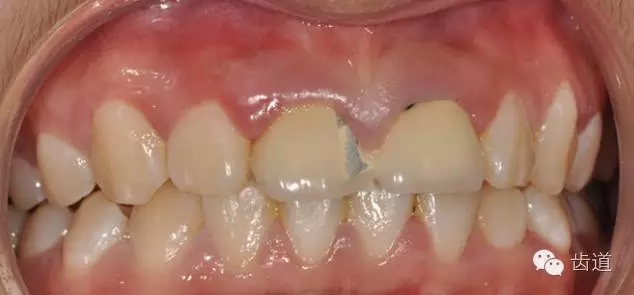

初診時(shí)口內(nèi)照

檢查:11、21烤瓷聯(lián)冠修復(fù)體,唇側(cè)部分崩瓷,可見(jiàn)金屬基底冠,邊緣不密合,牙齦紅腫,咬合緊,無(wú)明顯松動(dòng),X片示:11、21根管透射,根尖區(qū)陰影。